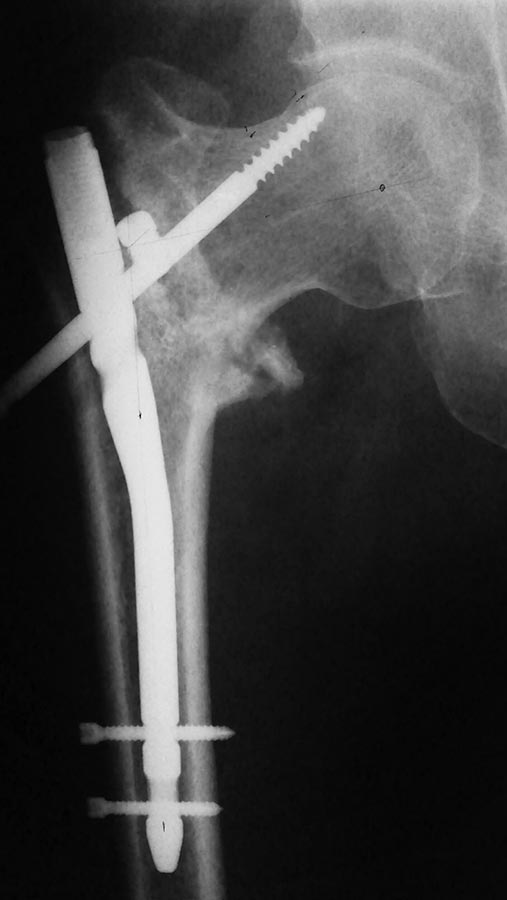

[Ortho] Чрезвертельный неправильно консолидирующийся перелом

Доброго времени суток! Анамнез без особенностей- мужчина 45-49 лет, не

алкаш, рработяга. В п\о периоде как уже писал миграция шеечного винта,

удаление его. Сначала вроде начал ходить с опорой, потом усилился б\с,

ходит с костылём. Вторая проекция.